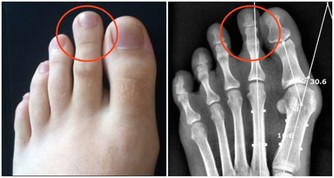

這句話講的是什麼意思呢?頸七椎向下相連的是胸椎的一椎、二椎,這兩個椎體與肺相通,是通往肺的通路,當頸椎扭傷一定牽連到胸椎的一、二椎;腰椎向上相連的是胸十椎、十一椎、十二椎,十一椎、十二椎與脾、胃相通,是通往脾胃的通路,當腰椎扭傷一定牽連到胸十、十一椎。

如此看來,我們在對頸椎錯位治療的同時,要顧及到胸椎的一、二椎的檢查和治療,腰椎錯位的治療,要顧及到胸椎的十、十一、十二椎的檢查和治療,與頸、腰椎相連接錯位椎體的治療,即是對本病的恢復起到治療作用,同時,也有利於頸、腰椎的治療。這些與之相連的椎體錯位,患者也一定會出現相聯繫臟腑的病症反應。以上對頸、腰椎檢查方法,對病症的判斷,以及治療的範圍,做為醫者不可不知也。

頸椎下端和腰椎上端的這些部位,往往是在臨床中被遺忘的角落,所以,既影響頸、腰椎的治療,也影響與之相連病症的治療效果。醫者在治療頸椎腰椎的同時,一定要檢查鄰近胸椎椎體的排列狀態,頸椎的治療要注意到肺(胸一、二椎),腰椎的治療要注意到胃(胸十、十一椎),這是治療頸椎腰椎病症的關鍵。